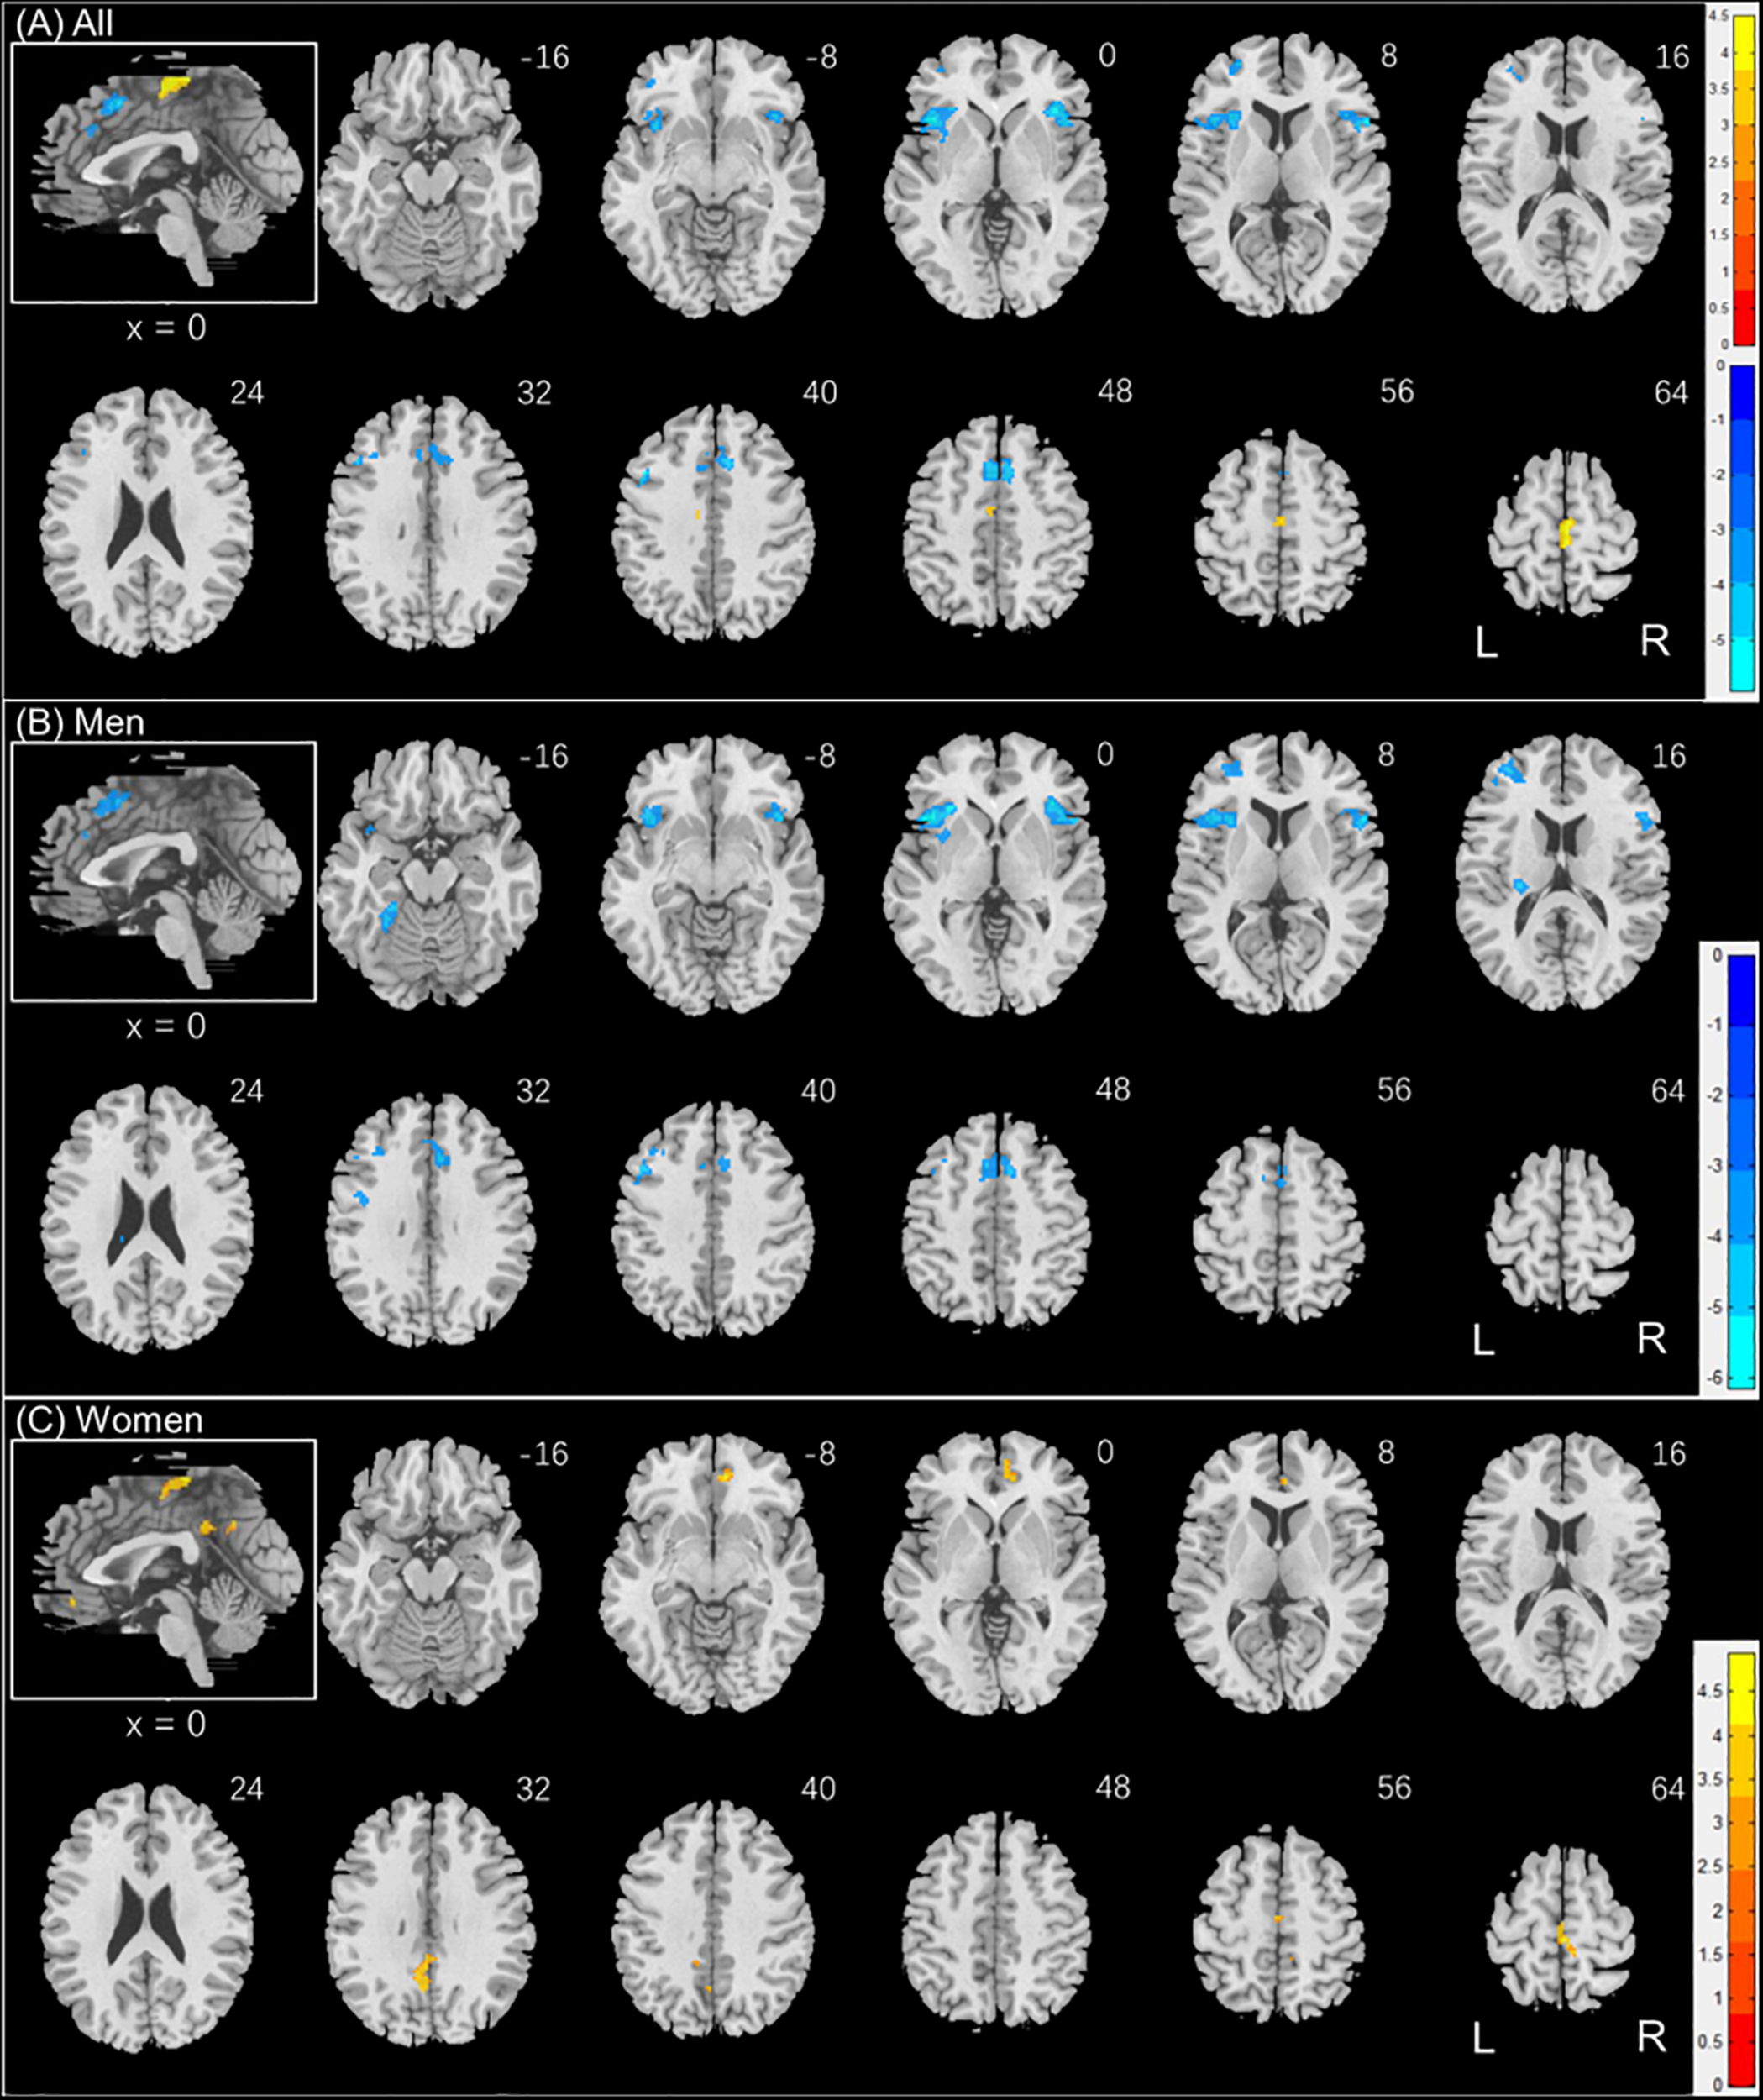

To examine sex differences, we conducted a two-sample t-test to compare men and women with age and years of education as covariates. At voxel p < 0.001, uncorrected, in combination with cluster-level p < 0.05, family-wise error corrected, men relative to women showed higher activation in the right superior temporal gyrus, bilateral occipital and posterior cingulate cortex, and precuneus (Figure 2). Women showed higher activation in the right inferior frontal cortex, as compared to men, during exposure to social vs. random interactions. These clusters are summarized in Table 2.

FIGURE 2

www.frontiersin.org

Figure 2. Sex differences in regional brain activations: two-sample t-test of the contrast (social – random) between men and women with age, years of education as covariates. Voxel p < 0.001, uncorrected. All clusters with cluster p < 0.05, corrected for family-wise error, are shown in Table 2. Color bars show voxel t values; warm: men > women, cool: women > men. Clusters are overlaid on a T1 structural image in neurological orientation: right = right. The inset shows a mid-sagittal section to highlight the clusters in the precuneus, posterior cingulate cortex and dorsomedial prefrontal cortex.

Table 2. Sex differences in regional activations to social vs. random stimuli.